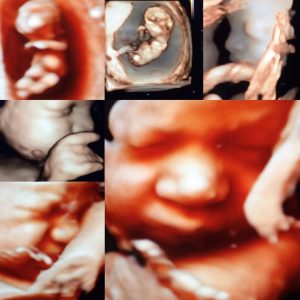

15134668_1378243818900722_3787905371689277491_n

Buradasınız: Anasayfa1 / Bebek Fotoları2 / 15134668_1378243818900722_3787905371689277491_n

• Ultrason Görüntüleri